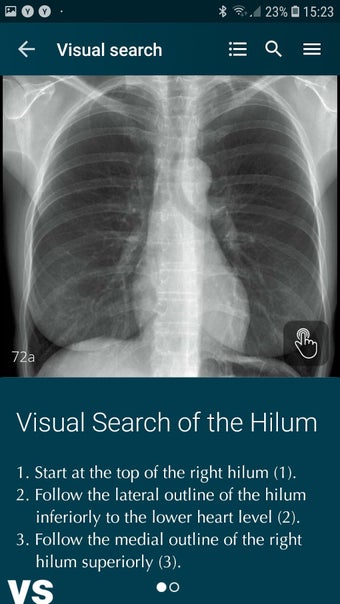

Radioloji'yi Keşfet: Göğüs Röntgeni Yorumlama, göğüs röntgeninin yorumlanmasının anlaşılmasını artırmak için tasarlanmış bir eğitim uygulamasıdır ve doktorlar, tıp öğrencileri ve radyologlar tarafından kullanılması amaçlanmaktadır. Uygulama, en küçük detayları görüntülemek için yakınlaştırılabilecek yüksek kaliteli görüntüler ve her bulgunun önemini anlamanıza yardımcı olacak bir sesli yorum içerir.

Ayrıca, uygulama bir hastanın göğüs röntgenini incelemeleri sırasında başvurabilecekleri bir dizi nasıl yapılır içerir. Uygulamadaki nasıl yapılır adımlarını takip ederek, kullanıcılar birçok farklı bulguyu doğru bir şekilde tanımlayabilecekler ve her birini bir hastalığın teşhisi için nasıl doğru bir şekilde kullanacaklarını öğrenebileceklerdir.